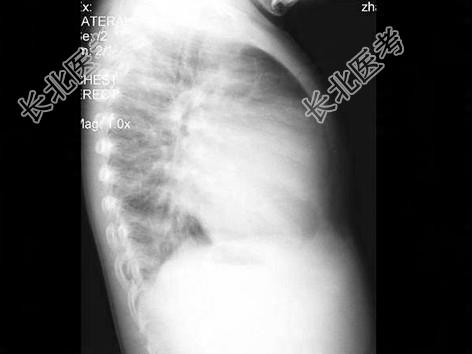

- 单项选择题男性,1岁零8个月, 生长发育差,易患呼吸道感染, 心悸气促,行心脏正、侧位片检查如图所示, 错误的是  (    )

A、正位示心影向两侧扩大,心尖左移

B、肺纹理增多

C、侧位示心前间隙变窄,心后食管前三角间隙消失

D、房间隔缺损

E、室间隔缺损